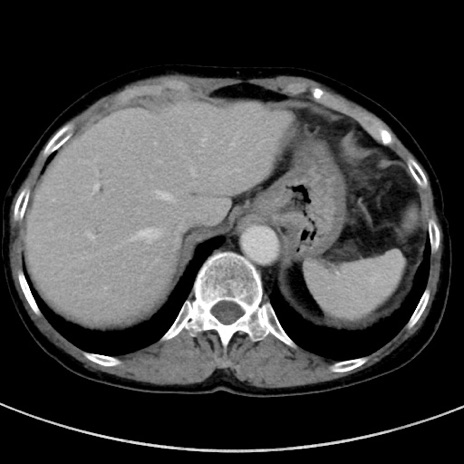

症例23(横断像)

【症例】70歳代女性

【主訴】下腹部痛・嘔吐

【現病歴】2日前より腹痛あり。昨日嘔吐あり。症状改善しないため来院。

【既往歴】胃GISTに対して胃部分切除後。

【身体所見】BT 37.1℃、BP 128/77mmHg、腹部:平坦・軟、下腹部に圧痛あり。

【データ】WBC 10200、CRP 0.31